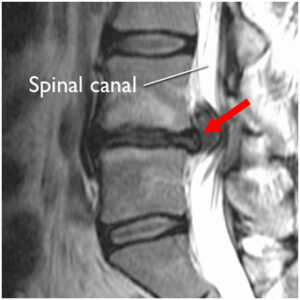

Neuroimaging. In addition, your doctor may make use of imaging such as MRI and CT scans to have a detailed look at the spine. This will allow your doctor to locate free fragments of the herniated disc easily.